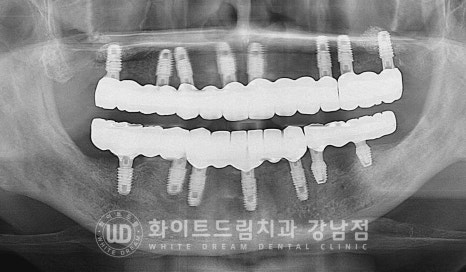

[동일 인물이며 동일 환경에서 촬영됨 / 치주염 전체임플란트 : 24.03.04 - 24.10.01 ]

x-ray를 보면 잇몸뼈의 상태가 적나라하게 보이는데요.

하악 앞니 쪽은 잇몸뼈가 폭탄을 맞은 것처럼 큰 구덩이가 패어있는 상태이고

상악 어금니 양쪽은 잇몸뼈가 거의 남아있지 않은 상태입니다.

그나마 다행인 것은 부분적으로 크게 무너진 상태여서

임플란트 식립이 가능한 상태였답니다.

잇몸뼈가 거의 다 녹으신 상태여서 최대한 잇몸뼈가 남아 있는 부위를 찾아서

식립하신 분입니다.

상악 어금니 부위 (16,26번 임플란트)는 상악동 거상술을 동반하였고

대부분의 임플란트는 모두 일반적인 뼈이식, GBR을 동반하여

식립을 진행하였습니다.

상악은 잇몸뼈가 부족할 때 상악동을 이용하여 모자란 잇몸뼈를 보강할 수 있지만

하악은 상황이 다릅니다.

하악은 하치조 신경관이라는 구조물을 무조건 피해서 식립해야 하기 때문에

신경관 위쪽으로 10mm 이상의 잇몸뼈가 있어야 일반적인 길이의 임플란트를 식립할 수 있습니다.

환자분처럼 신경관 위쪽으로 남은 잇몸뼈의 길이가 10mm 이내일 경우에는

조금 짧은 임플란트를 선택하여 식립하게 됩니다.

동일 인물이며 동일 환경에서 촬영됨

치료 기간: 24.03.04 - 24.10.01

정말 많은 뼈이식재를 이용하여 잇몸뼈가 소실된 부위를 최대한 복원하며